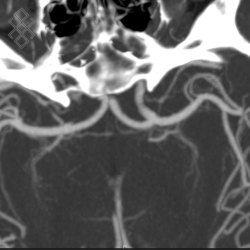

Angioscanner Cérébral